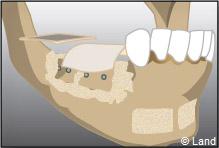

Les différentes étapes :

Prélèvement du greffon au niveau du site donneur

Apposition et stabilisation du greffon.

Recouvrement du greffon avec de l’os synthétique et une membrane

Après 6 mois de cicatrisation, il est possible de poser les implants qui recevront dans un deuxième temps les couronnes.

Apposition et stabilisation du greffon.

Recouvrement du greffon avec de l’os synthétique et une membrane